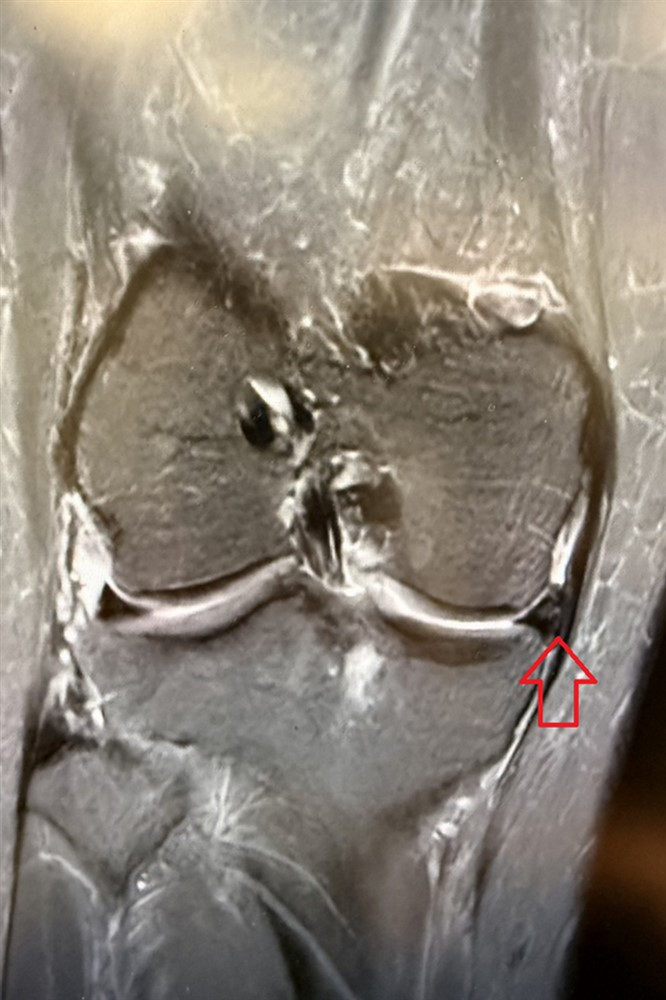

經過理學檢查、核磁造影檢查,發現是前十字韌帶斷裂,而內側半月軟骨卻不見蹤跡,懷疑是前一次手術的預後不佳導致碎裂。林坤輝醫師幫她進行「前十字韌帶重建及半月軟骨移植手術」,術後五天順利出院,並定期復健。

手術前,核磁造影檢查顯示半月軟骨消失(左);手術後半年,可見移植的半月軟骨(右)。圖/台北慈院提供